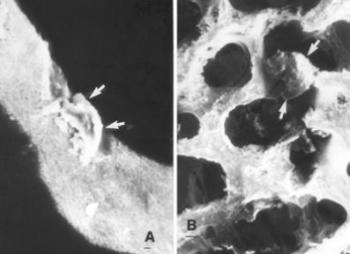

46. ábra. a) Gyógyult microfractura (nyíl) II. ágyéki csigolya testében. b) Tengelyeltéréssel gyógyult microfractura (nyíl) a csigolya trabeculáján. 11. század, senilis korú férfi. Sztereomikroszkópos felvétel. 20× nagyítás